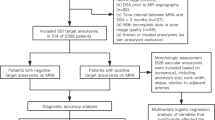

Intravenous FD-CTA imaging was performed after removal of the diagnostic catheter and introducer sheath about 25 to 30 min after the last DSA series. The patient was asked to close the eyes and to breathe calmly. A dedicated FD-CT program (DynaCT, Siemens AG, Healthcare Sector, Forchheim, Germany) with a mask run (native) and a second fill run (contrast-enhanced) rotation as described before [11] with an optimised contrast medium application method was used. Data acquisition per run was carried out using the following parameters: acquisition time 10 s per run, 70 kV, 512 × 512 Matrix, projection on 30 × 40 cm flat panel size, 200° total angle, 0.8°/Frame, 250 frames total, dose 1.2 μGy/Frame. To control contrast medium influx we used the bolus watching method [11] to visualise a proper time point to start the fill run acquisition as follows (Fig. 1): contrast medium injection is started 5 s after the start of the mask run. The mask run acquisition is completed within 10 s. The C-arm returns to the start position, this requires an interval of 5 s. It can be assumed that within 10 s contrast material injected into a peripheral cubital vein will not reach the cerebral arteries. After the C-arm returns to the start position (10 s after contrast medium injection) then standard 2D-DSA acquisitions are initiated at a rate of two images per second. When contrast opacification of the large arteries is visible the second rotation (fill run) is initiated manually. This method allows acquisition of the fill run with exact contrast material opacification of the arteries. We used 60 mL of contrast material (Imeron 400, Bracco Imaging, Konstanz, Germany) injected into a peripheral cubital vein at a rate of 5 mL/s using a power injector (MEDTRON, Saarbruecken, Germany) followed by a saline chaser (60 ml, injection rate 5 ml/s) [11].

The acquisition workflow is displayed in (a). The i.v. FD-CT acquisitions starts with the mask run (a, first black arrow). Five seconds later the contrast material injection followed automatically by saline chaser is initiated (red arrow, blue arrow). The C-arm returns to the start position (rotate back, second black arrow). Now bolus watching begins (third black arrow). If opacification of arteries is visible (red circle) the fill run is started manually (fourth black arrow). The procedure requires approximately 30 s depending on the bolus watching phase duration. Bolus watching is displayed in figure b to d. In the first image (b) the contrast material is not obvious. Four seconds later (c) opacification of arteries develops and after 6 seconds arteries are opacified perfectly (d). Then the fill run is initiated